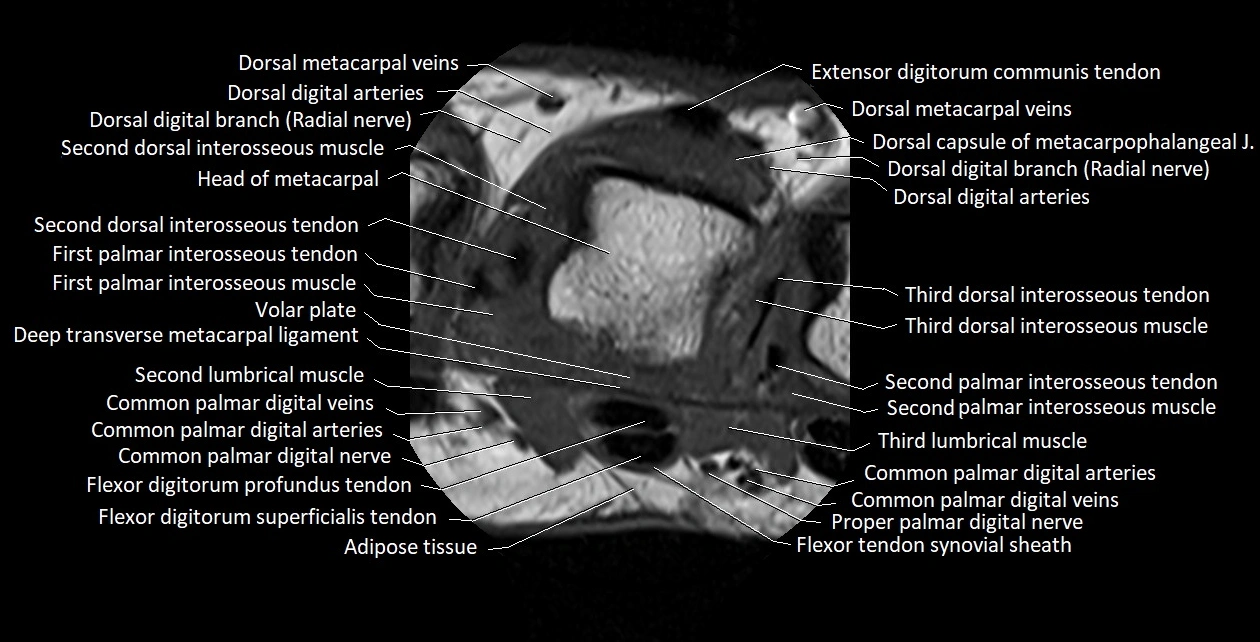

MRI images